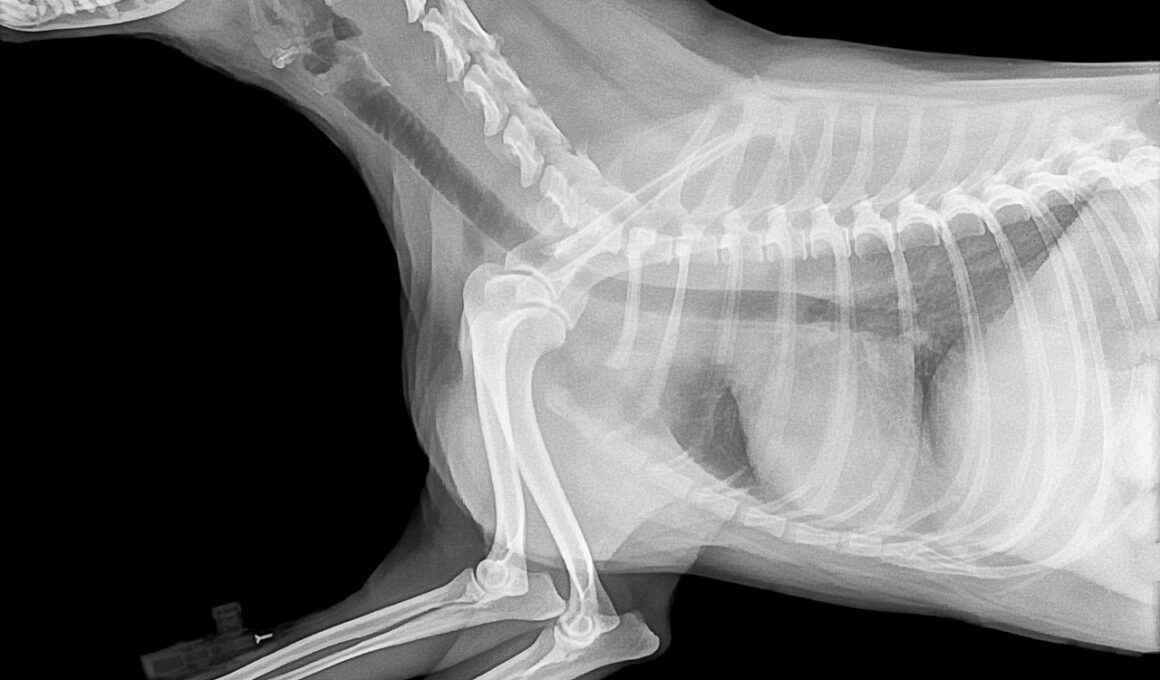

Common Symptoms of Bone Issues

Recognizing the symptoms of bone-related problems in pets can aid in early intervention and treatment. You may notice symptoms such as limping, difficulty getting up or lying down, or reluctance to engage in physical activities. Pain may not always be evident, but changes in behavior, such as increased irritability or changes in sleeping patterns, can signal discomfort. Swollen joints or lameness can indicate underlying problems such as arthritis or fractures. Additionally, watch for signs of decreased appetite or weight loss, which may reflect pain when moving. Regular veterinary check-ups can be instrumental in identifying these symptoms, especially for aging pets, before they worsen. Some pet owners may misinterpret reduced activity as a natural aspect of aging, but it’s critical to investigate these changes. Always be observant of your pet’s daily habits. If any unusual behaviors arise or if your pet appears to be in discomfort consistently, it’s time for a veterinary visit. Timely intervention can greatly improve prognosis and help prompt effective dietary adjustments and other essential treatment options.

Osteoporosis in pets can particularly pose a significant risk for older or small breed dogs and cats. This condition stems from various factors, including inadequate nutrition, hormonal imbalances, and genetics. These pets often exhibit difficulty during movements or may avoid jumping or climbing altogether due to perceived pain. Conventional treatments often include medication to manage pain and inflammation. However, integrating dietary interventions such as calcium and vitamin D supplementation can enhance the effectiveness of these treatments. Additionally, joint supplements containing glucosamine and chondroitin can support cartilage health and improve overall joint function. Regular exercise is also encouraged, as it fosters muscle strength while improving mobility. Tailoring your pet’s diet by including fortified foods or targeted supplements can significantly hinder the progression of bone-related conditions. Moreover, an enriched diet can optimize their overall health, improving vitality and reducing pain. Always follow your veterinarian’s guidelines regarding supplement types and dosages, ensuring your furry friend receives personalized care. In doing so, you’ll contribute positively toward enhancing their quality of life while addressing bone health concerns.